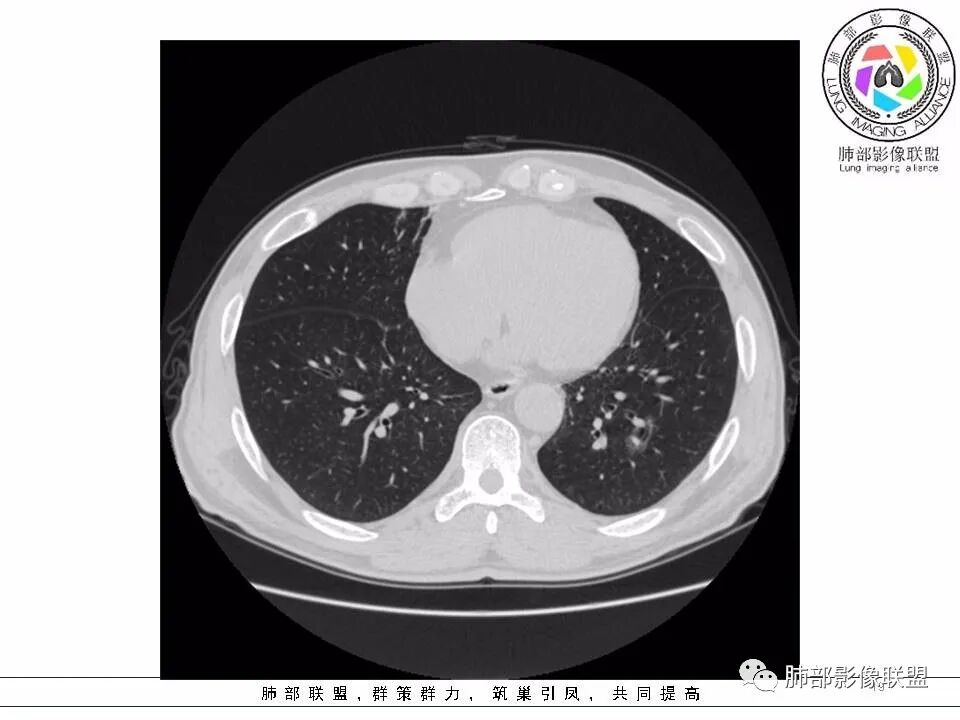

2.左肺下叶外基底段囊腔样病灶,轮廓柔和,壁厚薄不均,见壁结节。内见分隔或脊状突起。腔内见血管穿行。

这是有“故事”的囊!

3.囊壁外环以磨玻璃影,边界较清楚。

1.囊腔壁厚薄不均,壁结节,内有分隔,其内有血管穿行,指向新生物。

2.临近有边界清楚磨玻璃影,指向腺癌。